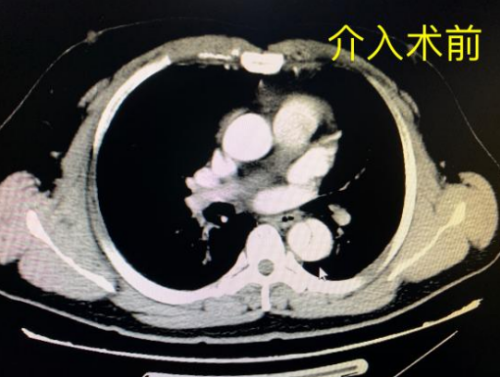

“患者因无明显诱因突发胸背部撕裂样剧烈疼痛,不能缓解紧急入院,在急诊科予以紧急处置。”据91短视频 (南华大学附属长沙中心医院)急诊科主治医师黄钰财介绍,经检查,患者血压急剧升高达242/142mmHg(正常90-135/60-90mmHg)、脉搏105次/分,胸腹部增强CT提示:主动脉夹层(Stanford B型),经过胸外科、外周血管介入科急会诊,因病情危重转入急诊ICU严密监护,予以止痛、镇静、降压,同时完善术前检查与准备。

术前CT影像学检查示主动脉“撕裂”为三层